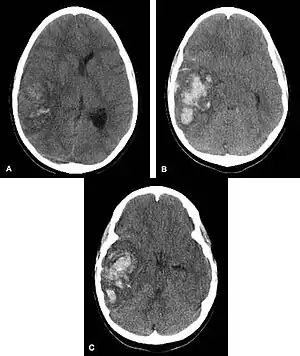

Hemorrhagic neoplasms are more complex, heterogeneous bleeds often with associated edema. These hemorrhages are related to tumor necrosis, vascular invasion and neovascularity. Glioblastomas are the most common primary malignancies to hemorrhage while thyroid, renal cell carcinoma, melanoma, and lung cancer are the most common causes of hemorrhage from metastatic disease.

Computed tomography (CT scan): A CT scan may be normal if it is done soon after the onset of symptoms. A CT scan is the best test to look for bleeding in or around your brain. In some hospitals, a perfusion CT scan may be done to see where the blood is flowing and not flowing in your brain.